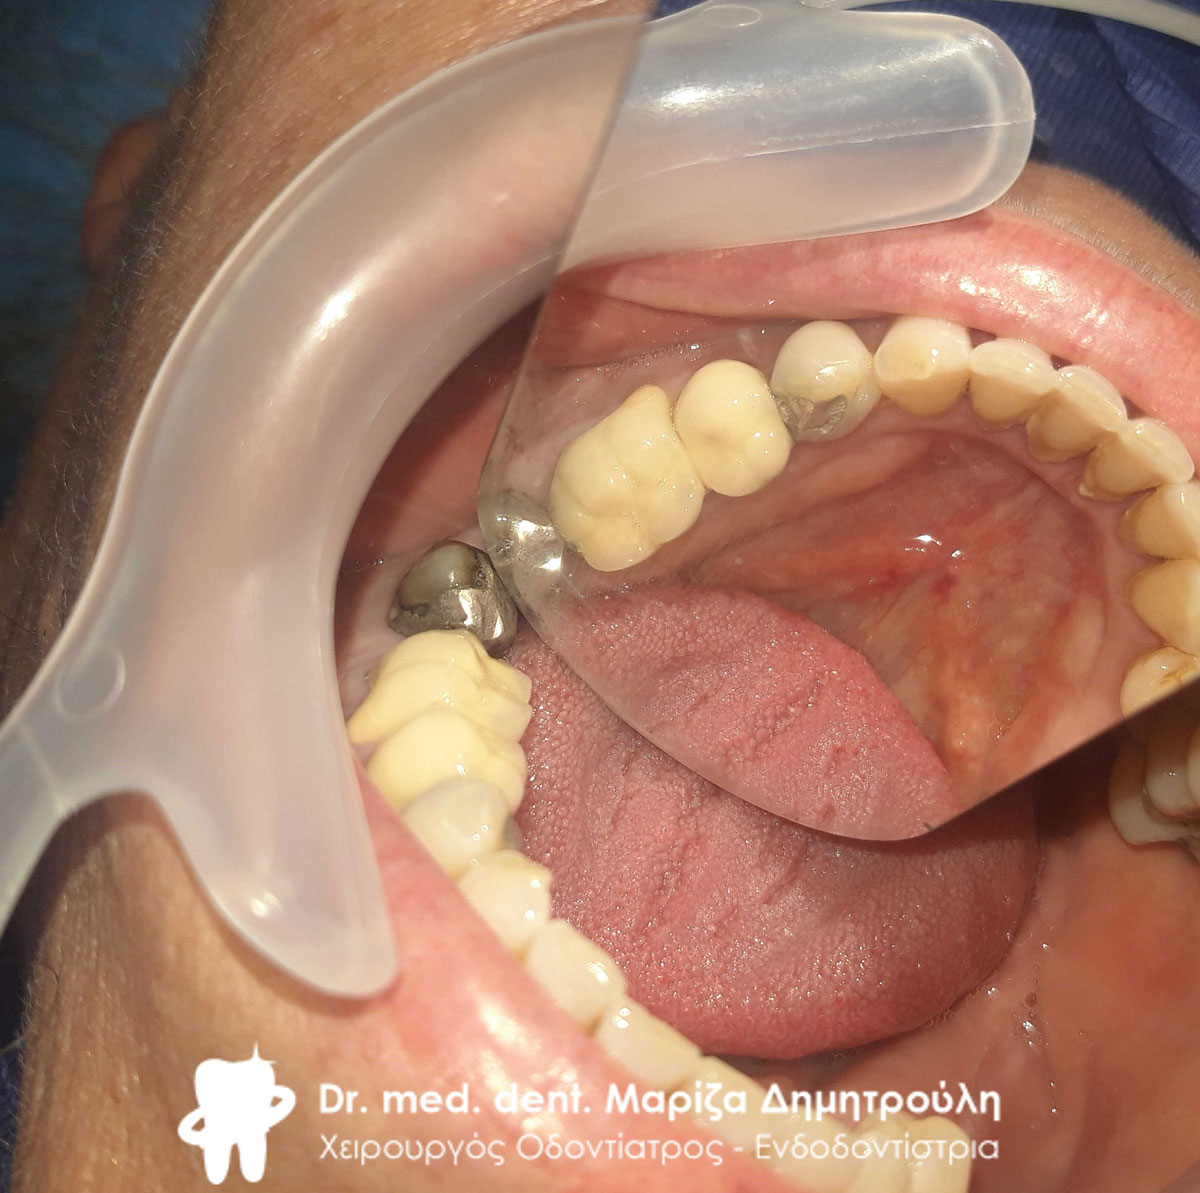

Τελική εικόνα όλων των δοντιών πριν τη λήψη αποτυπωμάτων

Τελική εικόνα όλων των δοντιών πριν τη λήψη αποτυπωμάτων

Εικόνα των δοντιών μετά τις απαραίτητες απονευρώσεις, ανασυστάσεις και εκτροχισμό τους

Εικόνα των δοντιών μετά τις απαραίτητες απονευρώσεις, ανασυστάσεις και εκτροχισμό τους